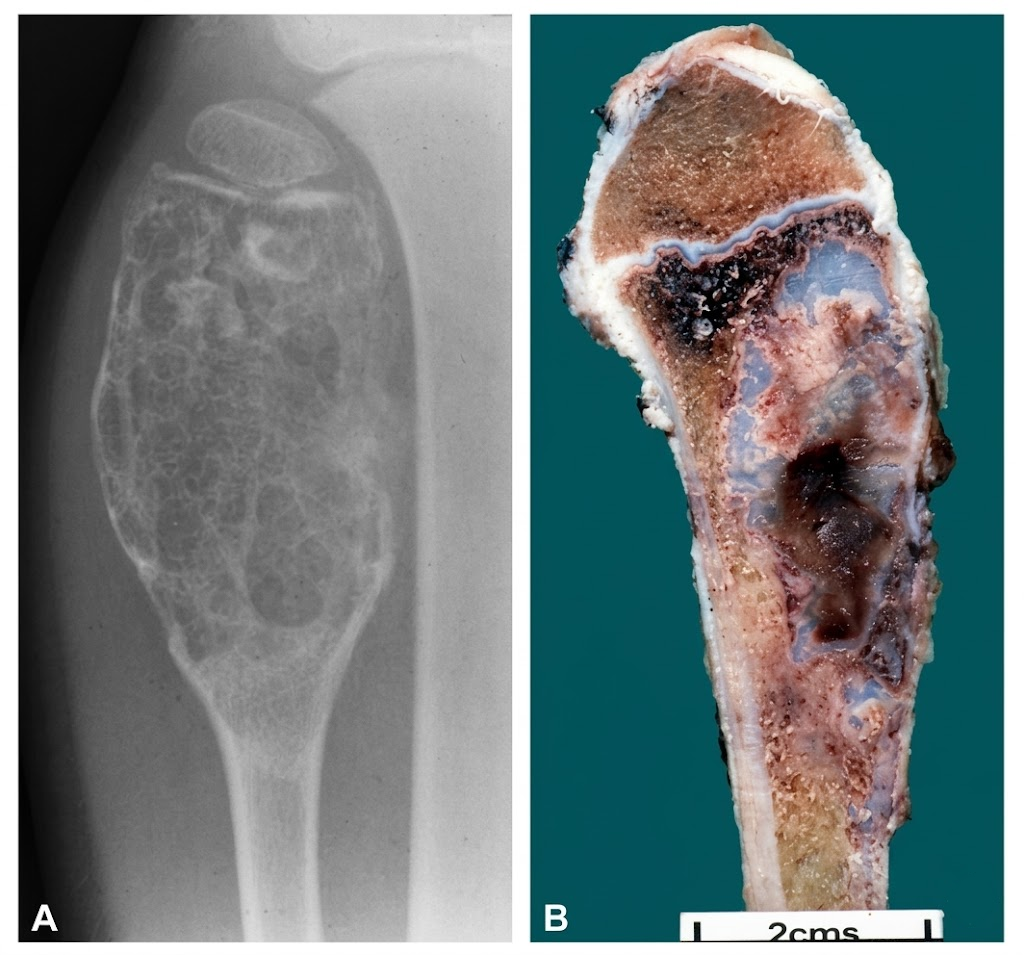

4.1 Radiografía simple

Suele mostrar una lesión lítica, de patrón geográfico, en región metafisaria, a veces excéntrica. Puede haber adelgazamiento/expansión cortical y, en algunos casos, calcificaciones condroides. La reacción perióstica no suele ser prominente.

5) Histopatología

En la práctica, el diagnóstico se apoya en un conjunto de rasgos relativamente constante: proliferación fusocelular blanda + nódulos de cartílago benigno + zonas con osificación endocondral “tipo placa de crecimiento”. Ese último punto (cartílago con arquitectura de placa de crecimiento) es el que más ayuda a separar FCM de otros tumores fibrosos.

5.2 Componente cartilaginoso

Aparece como nódulos de cartílago hialino sin atipia relevante. La característica más orientadora es que, en al menos parte del tumor, el cartílago puede organizarse en placas que recuerdan a la placa epifisaria, con osificación endocondral asociada.